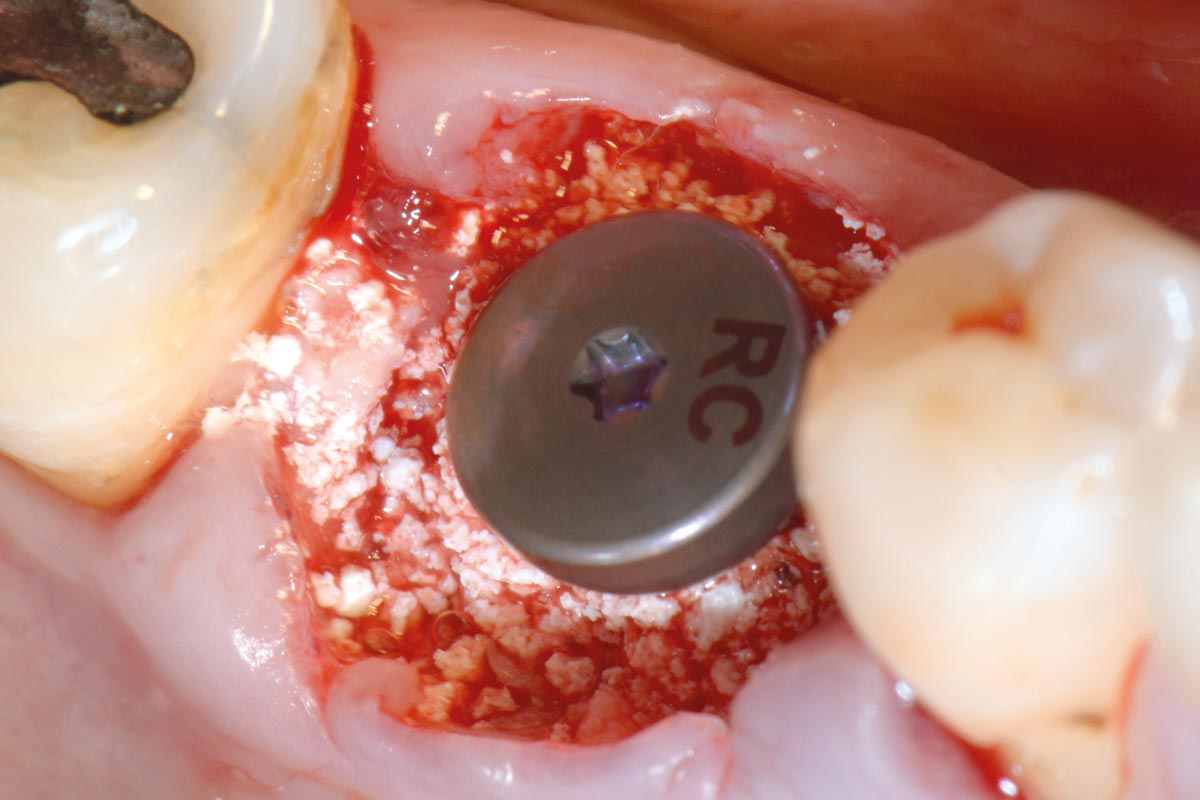

8/19 - Filling the gap around the placed implant with a mixture of maxresorb® and I-PRF

Immediate implant placement using maxresorb® - Dr. Alejandro Signorio